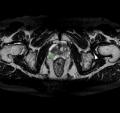

Callisto DataHub 2周年を記念し、専門医が作成した病変BBox付きの

肺がん疑いX線データセット 50症例と、病変セグメンテーション付きの

前立腺がんMRIデータセット(PI-RADS 4・5) 50症例を無料配布しています。前立腺がんMRIデータセットには、T1w, T2w, DWI, ADC, (あれば)DCEが含まれます。いずれも日本の医療施設由来で、所見文付き・商用利用可能なデータセットです。

前立腺がんMRIデータセット